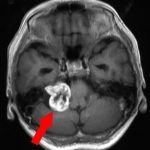

467

'23年9月

60代

小脳橋角部腫瘍

頭蓋内腫瘍摘出術

No.’23_101 手術前1

No.’23_101 手術前2